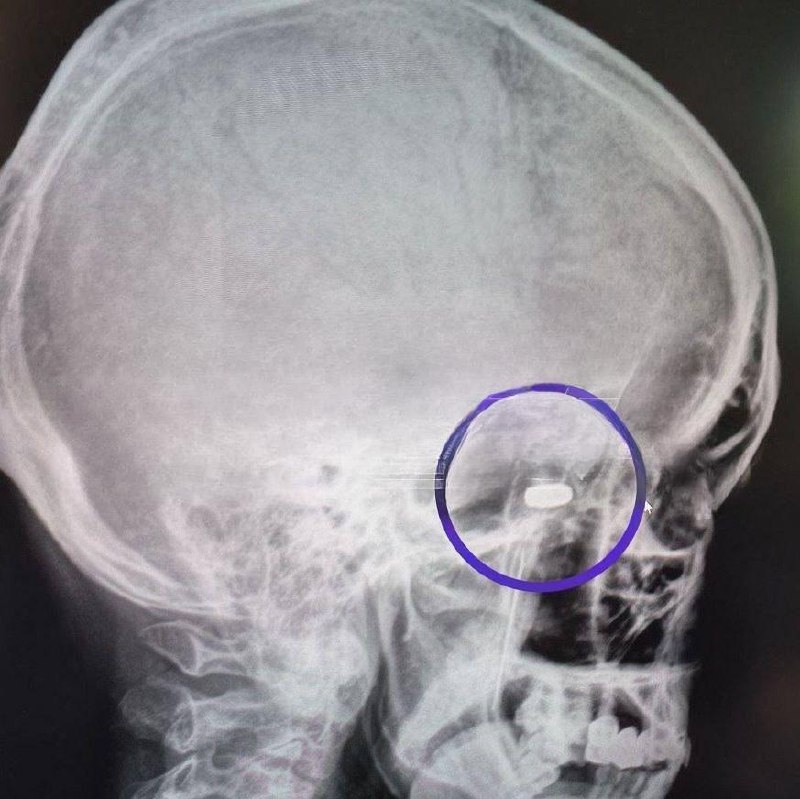

В Подмосковье мужчина выжил после выстрела в голову. Пуля чудом не задела жизненно важные органы и застряла в височной ямке.

70-летний россиянин из Московской области решил, что собирается уйти из жизни на своих условиях. Однако попытка самоубийства оказалась неудачной — не то подвёл самодельный огнестрел мелкого калибра, не то судьба решила, что ему ещё рано.

Пуля задела скуловую кость и срикошетила в височную ямку. Пробив мышцы, она остановилась перед костями черепа.

Деда срочно повезли в челюстно-лицевую хирургию Пушкинской клинической больницы, в результате экстренной операции пулю вытащили. Через несколько дней неудавшегося самоубийцу выписали домой.